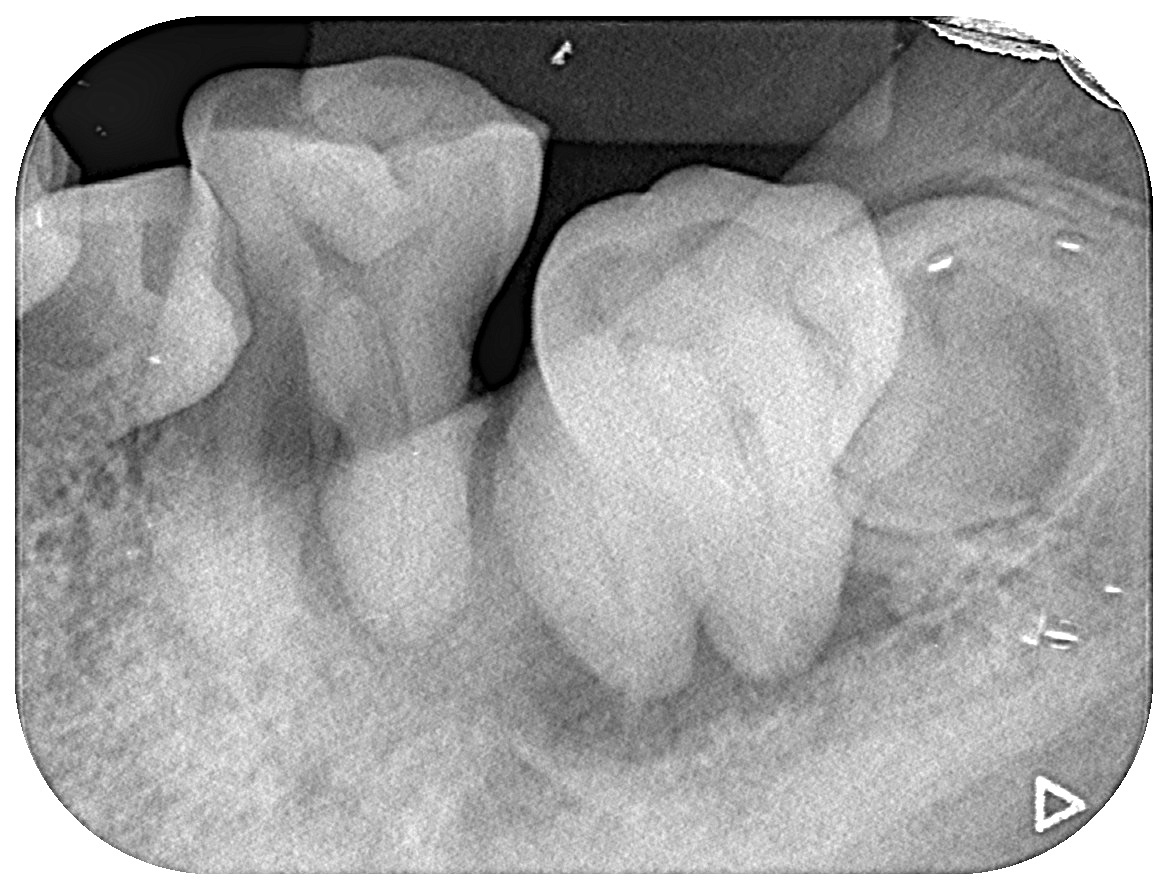

そのため当院では、患者さまごとにファイルを作り、口腔内写真や口腔内レントゲン、歯周病チャートや治療方針などを一括管理し、経時的変化もわかりやすく説明できるように努めています。また、できるだけ複数の治療方針をご提示して、患者さまに十分ご理解いただいた上で選択していただき、治療を行っていきます。

- “ご自分の歯で、長期間にわたって咬むことができること”を目標に、セルフケアとプロケアを行っていきます。当院では“むし歯”についても“歯周病”についても、患者さまの口腔内の状態を知っていただくために口腔内写真や丁寧な検査や歯の染め出し等による”見える化“を図っております。

ひとことで”むし歯“”歯周病“といっても、進行度合いや場所や範囲、咬み合わせの状況など、患者さまによりまちまちです。ですから、ご自分のお口の中の状態を良く知っていただき、適切なプラークコントロールの方法をセルフケア・プロケアの両面から、熟練した歯科衛生士により提案させていただきます。